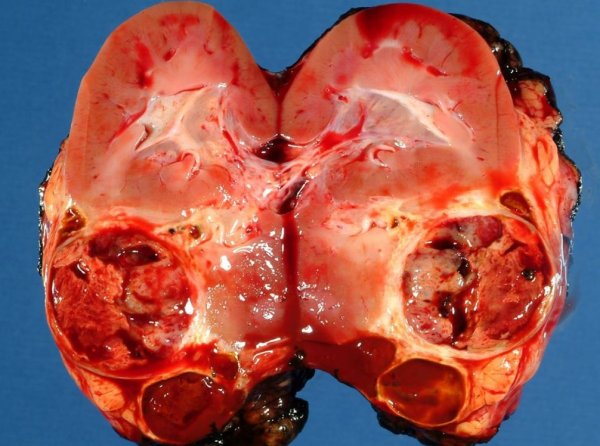

Выполнена операция: лапаротомия, удаление опухоли правой почки с ее резекцией. Гистологическое заключение: классическая нефробластома, промежуточная группа риска (см. рис. 4).

Рисунок 4. Интраоперационная фотография: резецированная почка (справа), опухолевый узел (слева).